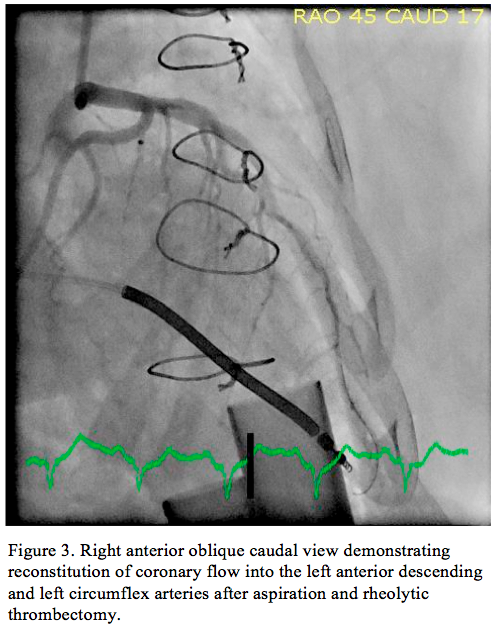

Coronary intervention was facilitated with heparin, dosed to a target activated clotting time of >300 seconds. A 6 Fr XB 3.5 guiding catheter was used to engage the LMT, through which a Prowater coronary guidewire (Abbott Vascular, Inc) was advanced into the distal LAD. A second Whisper coronary wire (Abbott Vascular, Inc) was advanced into the distal LCX. Manual thrombectomy was performed with an Export aspiration catheter (Medtronic, Inc) down the LAD, and then LCX. A large amount of thrombus was aspirated from each coronary vessel, successfully restoring TIMI 2 coronary flow. With thrombus clearance incomplete, an AngioJet rheolytic thrombectomy catheter (Medrad, Inc) was sequentially advanced into the LAD and LCX coronary

arteries with excellent results. Final angiography (Figure 3) demonstrated TIMI 3 flow to both coronary arteries. After the LAD and LCX vessels were cleared of thrombus, they had angiographically normal contours and were without dissection or atherosclerotic plaque. After the procedure, the patient was continued on aspirin and clopidogrel, and was initiated on warfarin with intravenous heparin bridging. She had no clinical signs of pump malfunction. A transthoracic echocardiogram demonstrated normal ventricular pump inflow and aortic outflow, with no significant aortic valve opening. Pump speed was slightly reduced to increase pulsatility and valve opening. She was managed conservatively with chronic anticoagulation and was discharged 8 days later on aspirin and therapeutic anticoagulation. At time